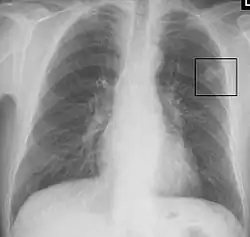

Mammogramm mit diagnostiziertem Brustkrebs

Konventionelle Röntgenaufnahme der Lunge mit einem Bronchialkarzinom